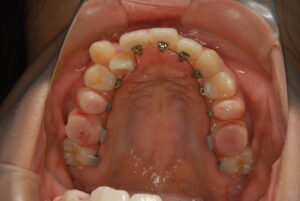

実際の症例紹介(20代女性/裏側ワイヤー矯正)

治療前

治療後

・主訴:八重歯と前歯の突出

・治療法:裏側からのワイヤー矯正(リンガル)

・治療期間:約1年半〜2年(目安)

・予想される副作用・リスク:装置装着後の違和感・疼痛、発音のしづらさ、一時的な咀嚼効率低下、ブラッシング不良によるむし歯・歯周病リスク など

※写真は代表的な症例です。口腔内の状態により治療法や期間は異なります。詳細は初診相談でご説明します。